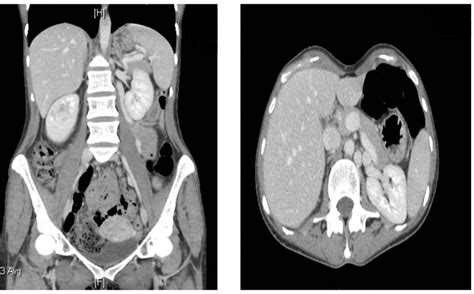

CT Angiography Provides a clear visual of the "nutcracker" anatomy and the compression of the vein.

To grasp why this syndrome causes such intense discomfort, it helps to visualize the anatomy. Under normal circumstances, blood flows freely from the kidney back to the heart. In Nutcracker Syndrome, the angle between the aorta and the mesenteric artery becomes too narrow, effectively "pinching" the left renal vein. This leads to increased venous pressure, which can cause the vein to swell and potentially lead to the formation of collateral veins as the body desperately tries to redirect blood flow.